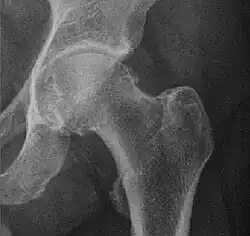

Crowe classification

In 1979 Dr. John F. Crowe et al. proposed a classification to define the degree of malformation and dislocation. Grouped from least severe Crowe I dysplasia to most severe Crowe IV.[13] This classification is very useful for studying treatment results.

Rather than using the Wiberg angle because it makes it difficult to quantify the degree of dislocation they used 3 key elements to determine the degree of subluxation: A reference line at the lower rim of the "teardrop", junction between the femoral head and neck of the respective joint and the height of the pelvis (vertical measurement). They studied anteroposterior pelvic x-rays and drew horizontal lines through the lower rim of a feature called "teardrop". The distance between this line and the middle lines of the junction between femur head and neck gave them a measure of the degree of femur head subluxation. They further established that a "normal" diameter of the femur head measures 20% of the height of the pelvis. If the middle line of the neck-head junction was more than 10% of the pelvis height above the reference line they considered the joint to be more than 50% dislocated.[13]

The following types resulted:[13]

| Crowe I | Femur and acetabulum show minimal abnormal development. | Less than 50% dislocation |

| Crowe II | The acetabulum shows abnormal development. | 50% to 75% dislocation |

| Crowe III | The acetabula is developed without a roof. A false acetabulum develops opposite the dislocated femur head position. The joint is fully dislocated. | 75% to 100% dislocation |

| Crowe IV | The acetabulum is insufficiently developed. Since the femur is positioned high up on the pelvis this class is also known as "high hip dislocation". | 100% dislocation |